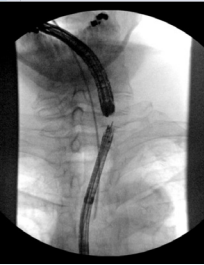

A 52-year-old male presented with a TEF more than 1.5 years following hospitalization for a severe COVID-19 infection. During this time, he required intubation and IMV for 69 days due to ARDS. His hospital course was complicated by two cardiac arrests, stroke, acute kidney injury requiring dialysis, osteomyelitis of the cervical spine, and sacral decubitus ulcers requiring colostomy diversion. Tracheostomy was performed and the patient was ultimately weaned from IMV. He made a significant recovery, but subsequently developed poor oral intake, chronic vomiting, and weight loss of 113 pounds. The patient was unable to swallow saliva and was completely dependent on his gastrostomy tube for nutrition. A modified barium swallow demonstrated a TEF with complete PES (Figure 2).

Figure 2 Modified barium swallow showing tracheoesophageal fistula with complete pharyngoesophageal stenosis and demonstrating aspiration of the entire bolus.

Figure 2: Modified barium swallow showing tracheoesophageal fistula with complete pharyngoesophageal stenosis and demonstrating aspiration of the entire bolus.